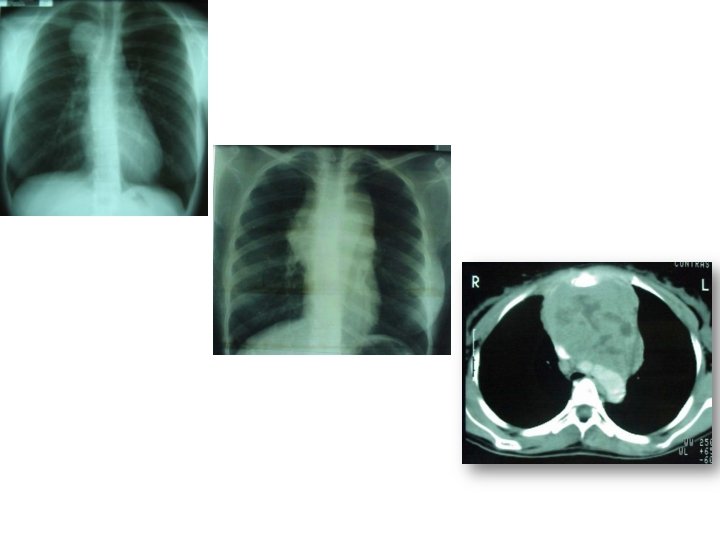

découverte sur la radio du thorax dans le cadre de la médecine scolaired’une hypertrophie médiastinale : opacité polycyclique, asymétique. siège médiastin antéro-supérieur. non compressive D. Bordessoule 2013

Imagerie - L'exploration du thorax et de l'abdomen par radiographie thoracique standard et scanner thoraco-abdominal et pet-scan est réalisée quelle que soit la présentation clinique initiale - L'échographie abdominale peut être utile notamment pour un suivi rapproché ou en cas de lésions nodulaires hépatiques. Sa sensibilité est cependant inférieure à celle du scanner pour les adénopathies abdominales et l'échographie ne dispense donc pas du scanner. - L'échographie cervicale est une méthode simple et fiable pour la mesure et le précis des adénopathies à l'étage cervical. Le scanner cervical est également un bon examen pour bien apprécier l'atteinte ganglionnaire cervicale. Un examen ORL spécialisé s'impose lorsque existent des localisations cervicales hautes ou spinales. -Histologie -recher par biopsie (non systématique de nos jour pour les Stades précoces si le pet-scan est négatif)